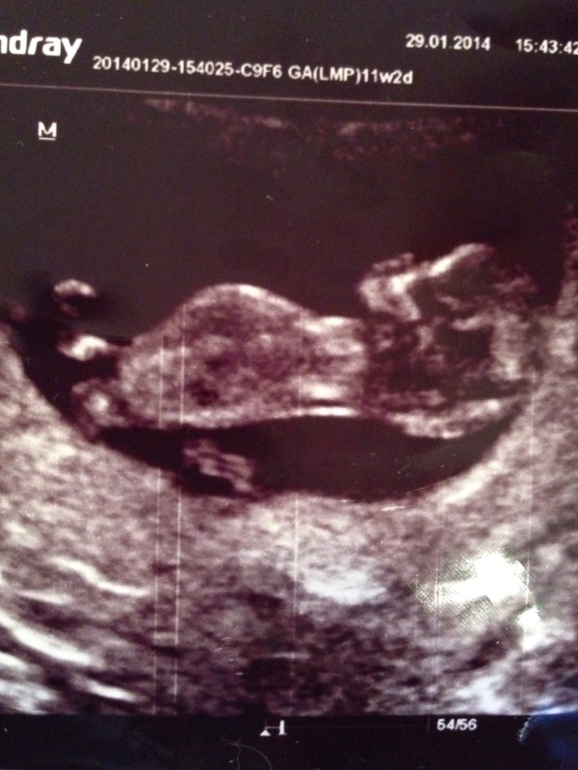

На 12 неделе видно пол

На 12 неделе видно пол 115 фото